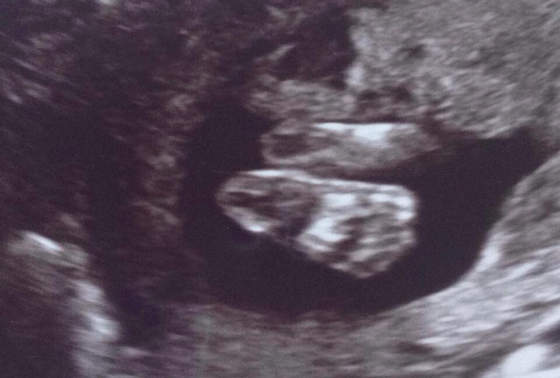

Ja ci powiem ze moja położna i usg ołówkowe było super ona widziała se chcemy malucha pooglądać i oprocz badan robiła takie zdjecia np

Zobacz załącznik 706077

Oczywiscie to moje kochane stopki ktore juz bym wycałowała :)

Potem mowila ze mamy czas to ona jeszcze pojeździ po brzuchu to mozemy do niej pogadac :) z 45 minut trwało samo usg hehehe